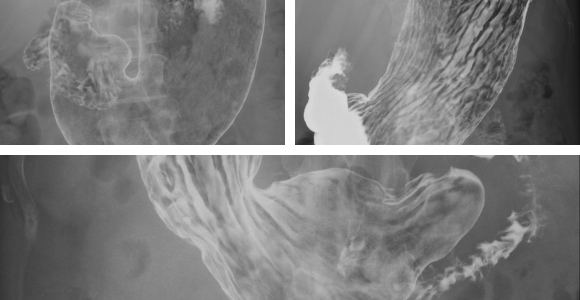

| 胃部X線検査 | バリウムを飲んで食道・胃・十二指腸を調べます。 |